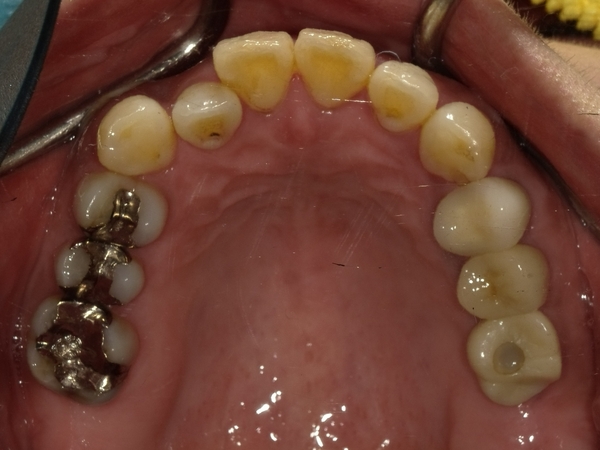

〇ご相談内容:上の前歯が内側に入っている、下の歯のがたつきが気になる〇矯正の種類:マウスピース型矯正「インビザライン」〇治療期間:14週間(約3ヵ月)〇治療費用:44万円(税込)